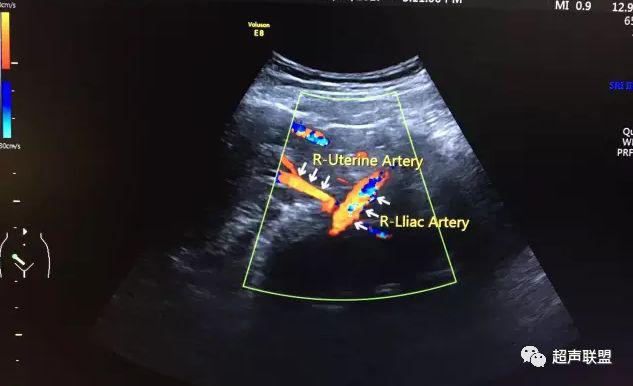

5 子宫动脉血流测定

正常妊娠时血流速度增加,血流阻力降落。缺氧早期的血流再分配,子宫动脉血流RI、PI值增加,阻力指数(RI)>0.57,子宫动脉血流频谱出现切迹。

3、子宫动脉标准:孕26或27周后,子宫动脉S/D>2.7,(RI)>0.57,有舒张早期切迹;

图7 正常中孕期子宫动脉频谱

图8 胎儿宫内缺氧,子宫动脉舒张早期可见切迹